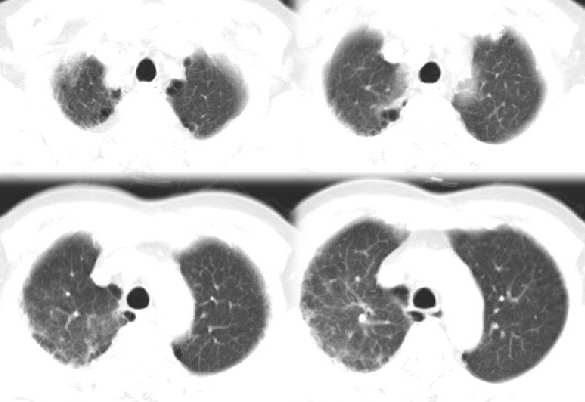

男54岁咳嗽咯痰2w,外院胸片示“右上大叶性肺炎抗炎治疗后部分吸收

右肺上叶少量间质炎性表现,结合病史为大叶性肺炎未吸收完表现。

结合病史,右上肺病变考虑炎症,继续抗炎治疗后复查;

该病人54岁,胸膜下可见多个类圆形透亮影,是不是还要考虑慢性/弥漫性肺疾病可能?

右肺上叶少量间质炎性表现,大叶性肺炎吸收期。

考虑还是弥漫性间质性改变伴右肺炎症